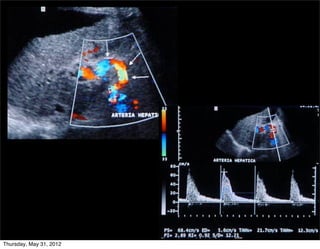

Arteria hepática (AH) normal

• Abordaje: intercostal

• 20% flujo hepático

• Baja resistencia (flujo

diastólico anterógrado)

• IR: 0.5-0.7

• VPS: 30-60 cm/seg